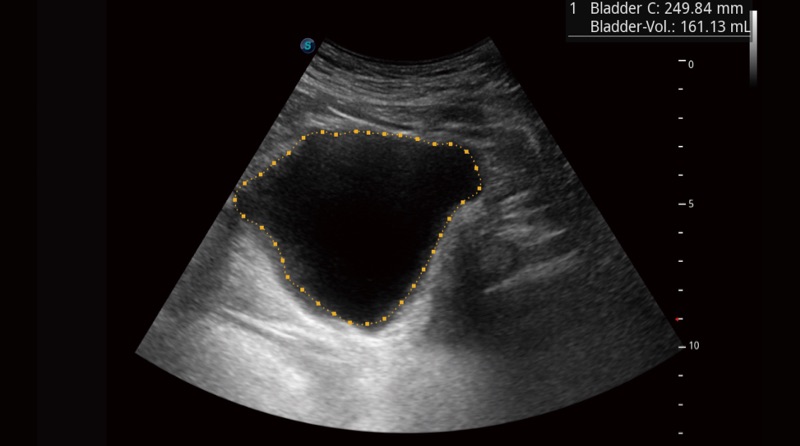

Auto Bladder ermöglicht mit nur einer Schlüsseltrassierung der Blasenwand und Volumenmessung effizientere und präzisere Konturen und Ergebnisse, unabhängig von der Form und Größe der Blase.